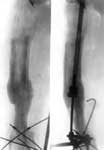

3.Больной в аппарате Илизарова.